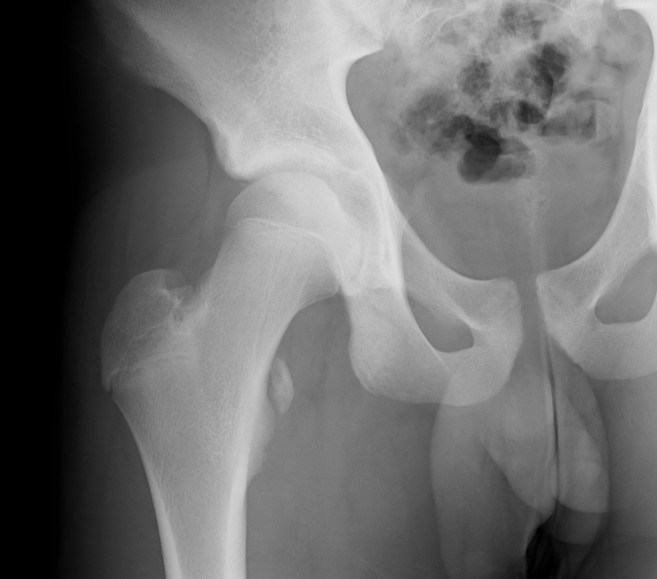

AIIS Avulsion

Attachment

Rectus femoris

Issues

1. Can develop hip impingement / subspine impingment

2. Heterotopic ossification